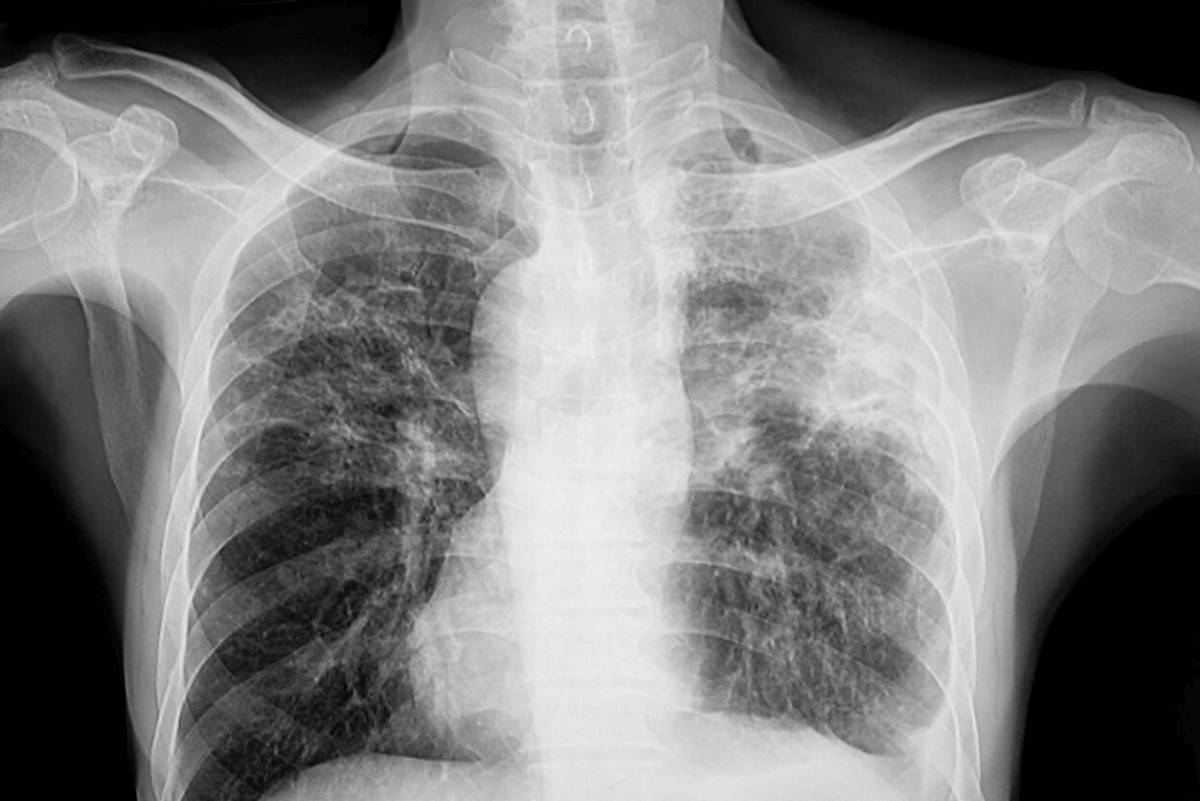

Verem, hava yoluyla bulaşan Mycobacterium tuberculosis bakterisinin sebep olduğu ve genellikle akciğerleri etkileyen bulaşıcı bir hastalıktır. Yani veremin etkisi sadece akciğerlerle sınırlı değildir; bu hastalık kemikler, böbrekler veya lenf bezleri gibi vücudun başka kısımlarını da etkileyebilir. Veremin, hava yoluyla bulaştığını söyledik. Örneğin aktif verem hastası bir kişi öksürdüğünde, hapşırdığında veya konuştuğunda, havaya küçük damlacıklar saçar. O kişi ile aynı ortamları paylaşan kişilerin bu damlacıkları solunmasıyla verem onlara da bulaşabilir.

Veremin başlıca belirtileri iki haftadan uzun süren öksürük, ateş, gece terlemesi, iştahsızlık ve kilo kaybıdır. Ayrıca göğüs ağrısı ve kanlı balgam da görülebilir. Evet, veremin tedavisi mümkündür ve genellikle başarılıdır. Tedavi, birkaç farklı antibiyotiğin genellikle altı ay veya daha uzun süre boyunca düzenli olarak kullanılmasını içerir. Bu süreçte hekimin talimatlarına kesinlikle uyulması hem hasta hem de hasta yakınları için büyük önem taşır.